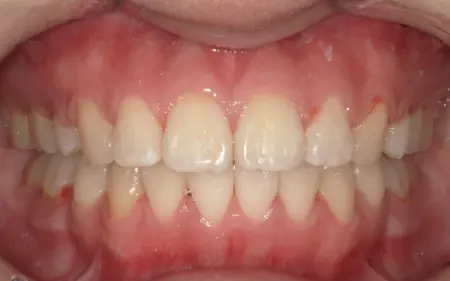

2025.11.0920代女性 マルチブラケット装置やヘッドギアを併用した矯正治療で出っ歯を改善した症例